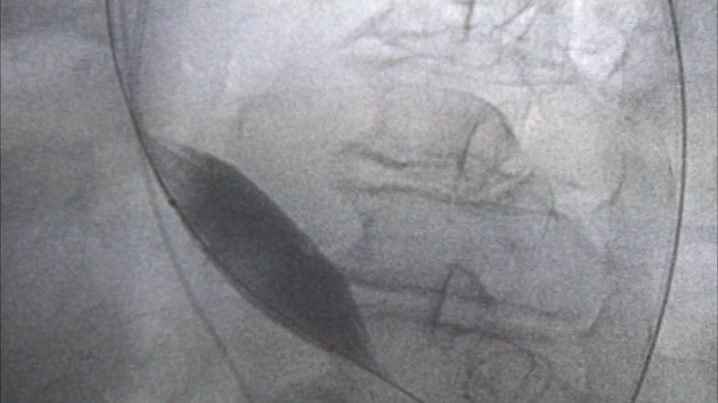

prywatna służba się jednak sprawdza. straszne jak się widzi do czego prowadzi wprowadzanie ludzi z polityki do zarządu szpitala w Tczewie...

Dr Wilczewski SUPER LEKARZ